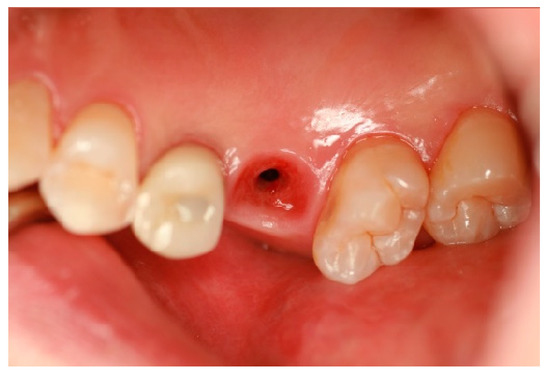

Figure 1 highlights the importance of a carefully designed emergence profile in achieving a natural and biologically stable peri-implant soft tissue interface. In SPI cases, ensuring seamless soft tissue adaptation to implant restoration is critical. By placing coronal flaring submucosally, the transition between the implant and the soft tissue more closely mimics that of natural dentition, enhancing both esthetic and functional outcomes. However, this approach inevitably results in an extended and broader transitional zone within the peri-implant soft tissue.

Figure 1.

The upper first molar was replaced with an implant-supported restoration following the extraction of the natural tooth due to a periapical abscess. The replacement successfully restored both function and esthetics. Notably, attention should be given to the junction between the tooth structure (white) and the soft tissue (pink) in terms of their spatial relationship and proportional dimensions. Although the emerging part of the implant restoration is not externally visible, for a natural appearance, the emergence profile beneath the peri-implant soft tissue must align precisely with the same location and diameter as the cervical area of the neighboring natural teeth. This ensures that the implant restoration maintains continuity with the marginal gingiva at the soft tissue level and the cervical region of the adjacent natural teeth, achieving seamless integration within the oral environment.

For an implant restoration to achieve a natural appearance, the peri-implant soft tissue (pink) and the cervical portion of the implant restoration (white) must be proportional in size and aligned harmoniously with the gingival levels of adjacent teeth. As long as the surrounding gingiva remains healthy, ensuring this precise correspondence from the very first visible point of the restoration supports seamless and natural-looking integration within the oral environment (Figure 1).